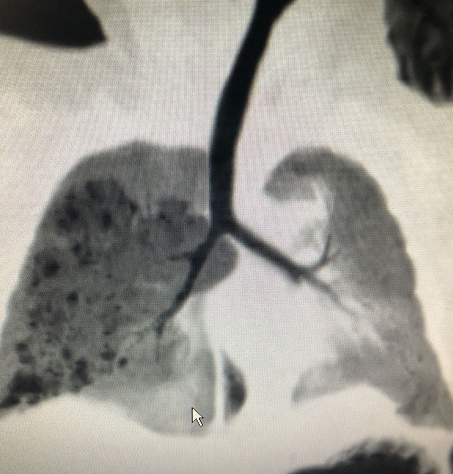

建议术前要有一次的CT检查,以明确病变所在肺段,对于手术切肺叶还是切肺段、肺亚段、联合亚段等提供有利帮助。增强CT主要是用于分辨病变的血管供应。随着胎儿肺部超声的发展,病变部分的血管可以用彩超来诊断,关于胎儿肺部超声可能大家知道的很少,我会在随后的科普中再专门和你们说。

如果反复出现感染,有可能使得病灶内积聚大量炎症,特别是II型、III型的肺囊腺瘤,手术时我发现这些宝宝的中至大的囊泡内总会积脓。 如果生后没有反复肺炎,亦不用反复检查,出现气喘、呼吸困难的时候再及时复查便可。

至于切掉之后,我们如果采用的是肺段或者肺亚段切除,保留了大量的正常肺组织,那宝宝的肺功能和肺容积会恢复得很快。我院所有的术后宝宝过一个月过来复查的胸片或CT以及肺功能都提示已经恢复到正常宝宝的水平。